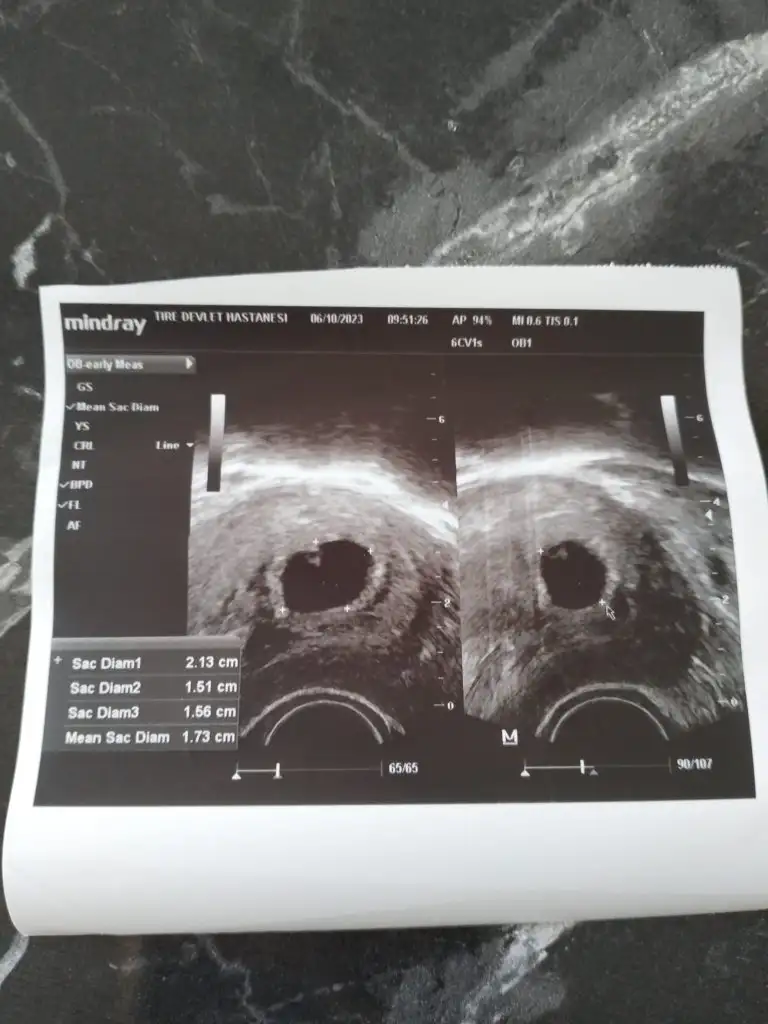

Vajinal ultrason bana da bakar mısınız lutfenYerleşim yeri erkek ama kemik yapısı kız. Bence minnoş bir kız olacak6-7 haftalık usg görüntüsü varsa ona da yorum y